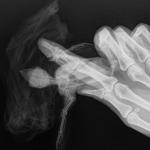

Врач сказал, вывих плеча, когда трогаешь чувствуется как там все смещается (((, и перелом лучевой кости, со смещением,наложил крестообразнуе повязку и крыло примотал к телу иначе сустав будет смещаться. Посмотрите пожалуйста снимки и подскажете что делать ??????

post-61846-1436378449_thumb.jpg post-61846-1436378467_thumb.jpg